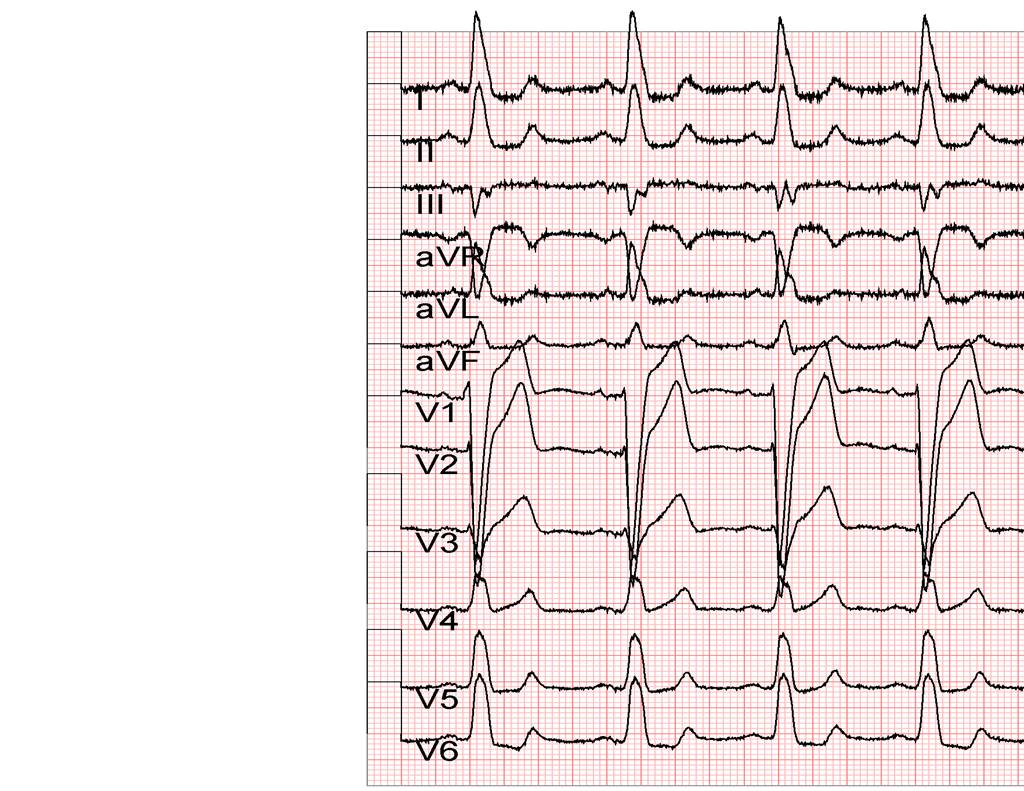

ECG(2014/5/14)

全胸片

◆完全性左束支传导阻滞

◆ECG: CLBBB

◆ECG:窦性心律,CLBBB, QRS 158ms

◆ECG: 窦性心律,完左消失,QRS 98ms

◆ECG: 窦性心律, HR 67bpm, QRS 98ms

◆ECG: 窦性心律,HR 66bpm, QRS 正常